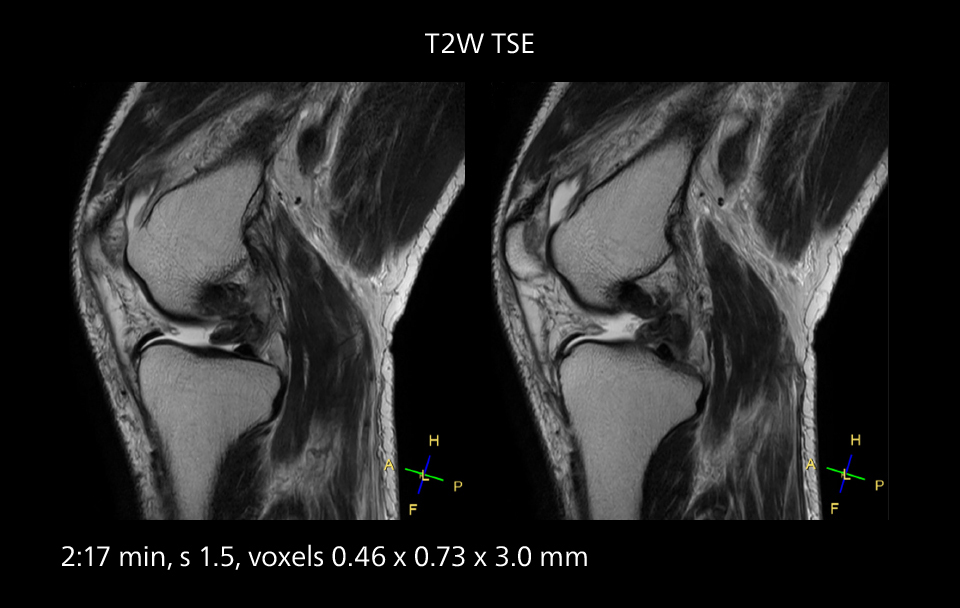

Sannodai Hospital radiologists had been very satisfied with their Ingenia 3.0T with Compressed SENSE, however after acquiring SmartPath to Elition X they have demonstrated improved image quality and even higher speeds in imaging studies throughout the body, according to Dr. Makuuchi. “Generally, we were impressed by seeing that images are very sharp and have higher SNR than we used to get with our Ingenia 3.0T system,” he notes. “We were delighted to see that high image quality can be obtained in a short time thanks to the Elition with its powerful An example of increased imaging speed is in knee studies. “There is a definite scan time reduction for T2* mFFE and proton density TSE – both of these sequences benefit from much shorter repetition times,” he reports.

gradients. Some high resolution examinations that were not possible before dueto their longer scan time, are now routinely performed with the upgraded system.”

Overall, imaging time per sequence has been reduced since the Elition X upgrade. This can help reduce the risk of patient movement and the need for rescans. “As our hospital has many elderly patients, we consider it important to obtain high-quality data in a short time,” Dr. Makuuchi says. “Shorter imaging times are also useful for accepting emergency patients, because faster emergency studies have a reduced impact on the daily examinations schedule. In emergency cases it is also important that high quality images are obtained in a short time.”